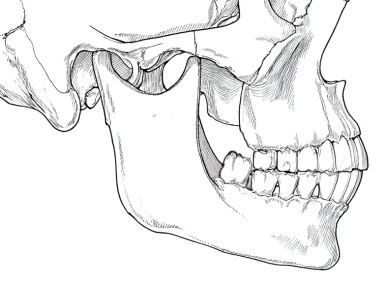

3.上顎と下顎の噛み合わせる歯がどちらかにない時は歯がだんだん伸びてきて、顎の運動を邪魔してしまい、関節が痛くなることがあります

きっちりした良いかみ合わせですが、一部奥に親知らずがあります。上顎にかみ合う歯が無いので、だんだん上へ伸びています。

下顎を前の方へ動かしたとき、伸びている親知らずは上の歯とぶつかってしまいます。こんな時、スムーズな顎の運動が出来なくなり、関節が痛くなります。